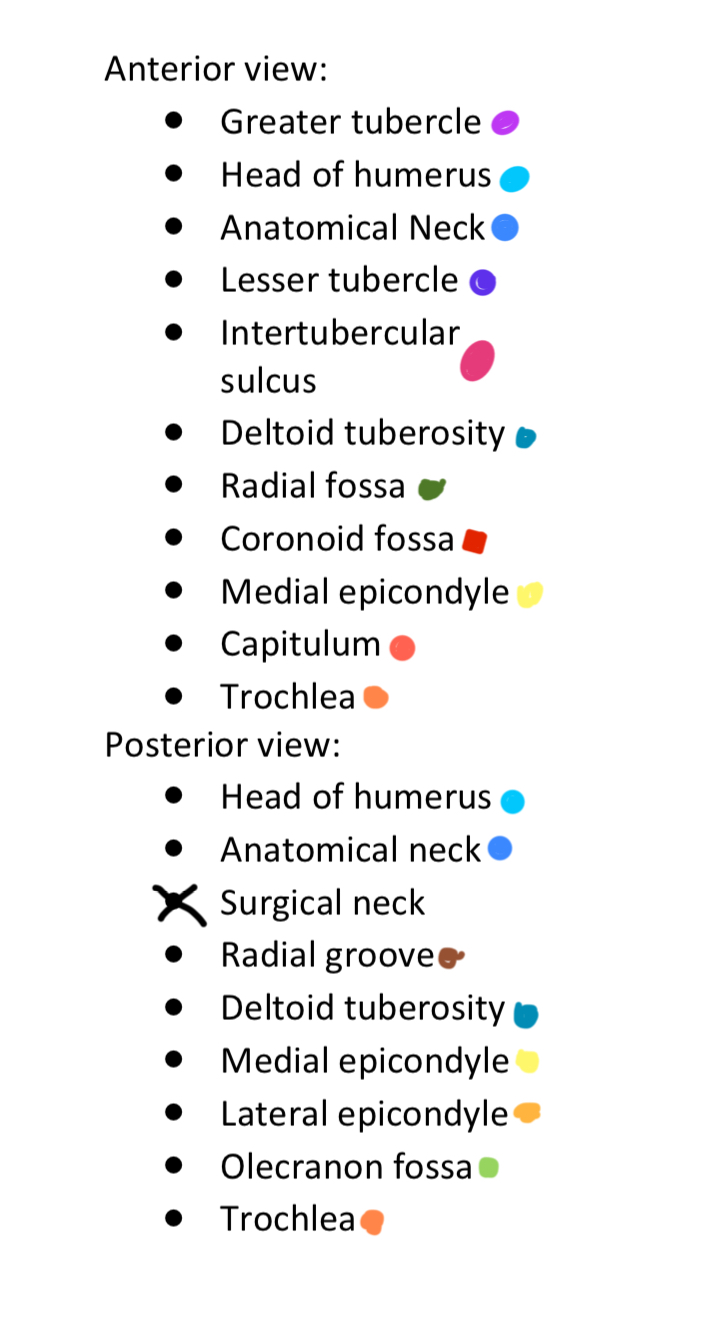

Anterior & Posterior Views of the Humerus

14 Terms

1

New cards

Light Purple

Greater Tubercle

2

New cards

Light Blue

Head of Humerus

3

New cards

Dark Blue

Anatomical Neck

4

New cards

Dark Purple

Lesser Tubercle

5

New cards

Pink

Intertubercular Sulcus

6

New cards

Cyan

Deltoid Tuberosity

7

New cards

Dark Green

Radial Fossa

8

New cards

Red

Coronoid Fossa

9

New cards

Yellow

Medial Epicondyle

10

New cards

Salmon

Capitulum

11

New cards

Dark Orange

Torchlea

12

New cards

Brown

Radial Groove

13

New cards

Light Orange

Lateral Epicondyle

14

New cards

Light Green

Olecranon Fossa